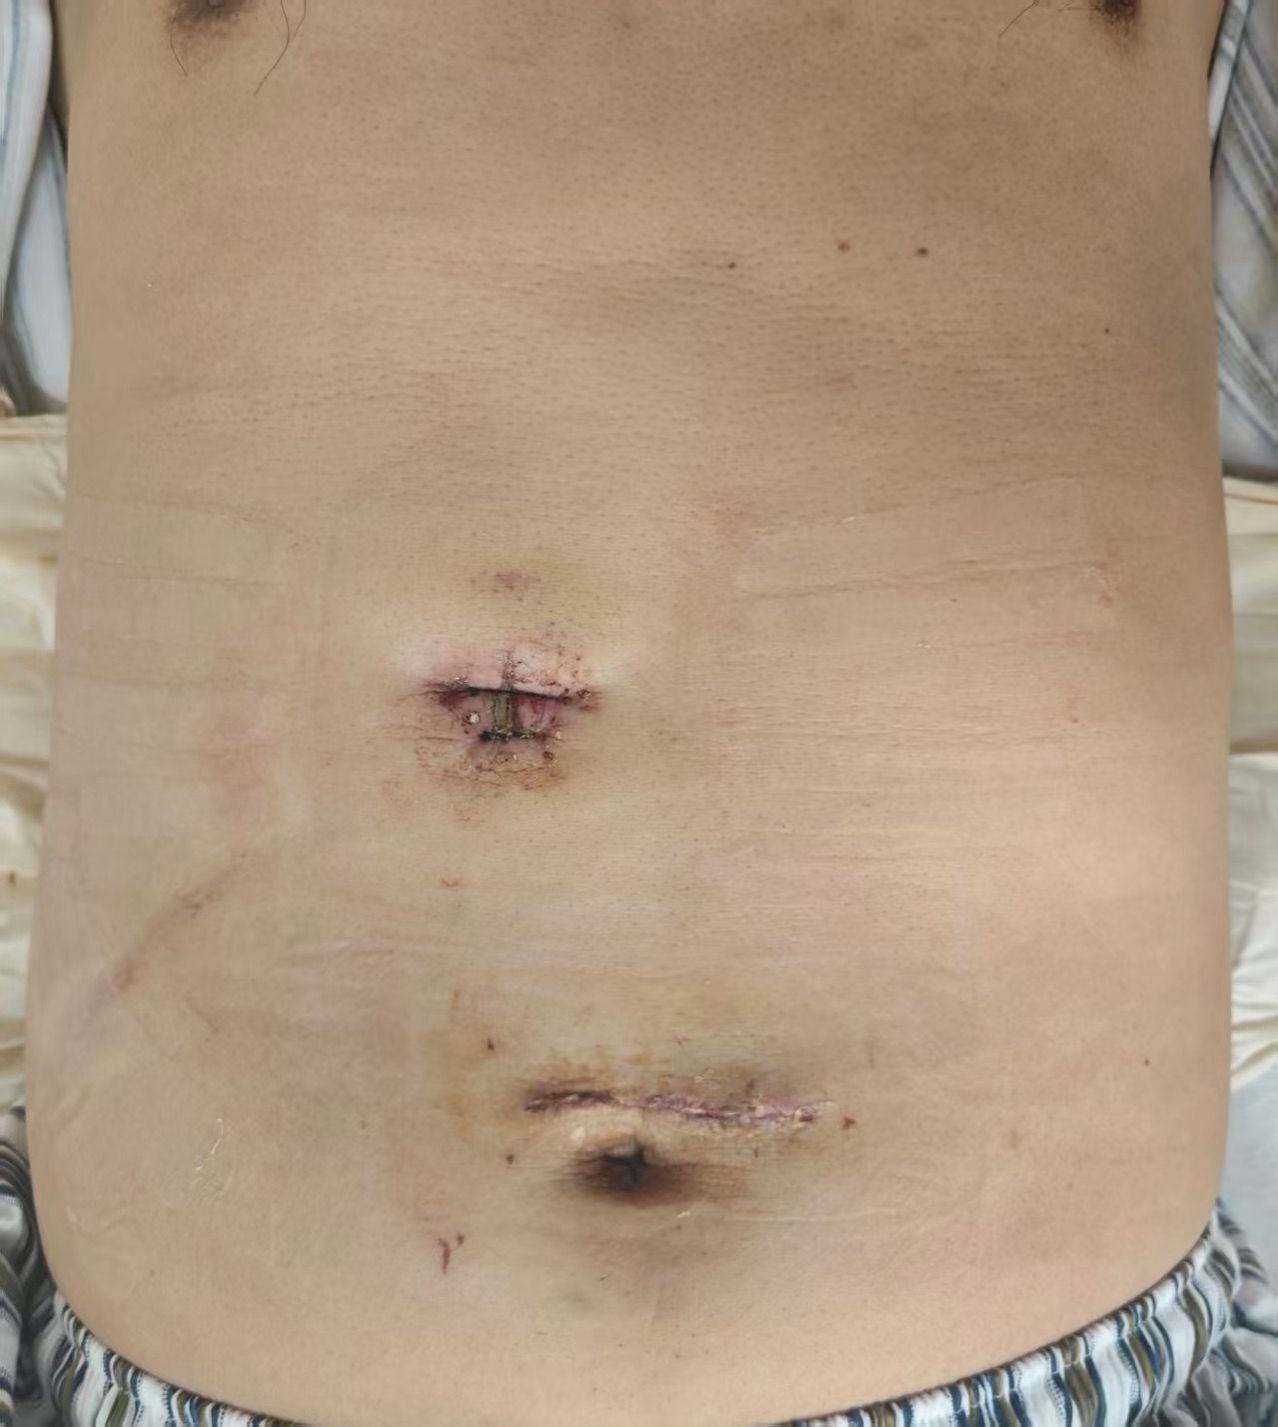

与传统腹腔镜手术需要在腹壁上开多个孔洞不同,单孔机器人手术仅通过一个约3厘米的小切口置入所有手术器械和摄像镜头。在狭小的单一切口空间内,蒋安主任医师娴熟操控国产“精锋”机器人手术系统,其放大的3D高清视野、可540度旋转的机械臂,极大地超越了人手的灵活性和稳定性,成功克服了操作角度受限、器械相互干扰等世界性难题。蒋安教授和曲凯教授在术中精准地分离肝脏组织、结扎血管,完整切除了包含肿瘤的肝左外叶,整个手术过程流畅,仅耗时3小时,出血量仅50毫升。

“这是一次技术上的跨越。”术后主刀医生蒋安主任医师介绍,“单孔机器人肝切除是肝胆外科领域的新技术。与传统开腹或多孔腹腔镜手术相比,它最大的优势在于‘极致微创’——只有一个切口最多另加一个引流管口,且常选择在肚脐等隐蔽位置,术后几乎看不到疤痕,极大地满足了患者对美观的需求。同时,它还能显著减轻术后疼痛,缩短住院时间,加速患者康复。”